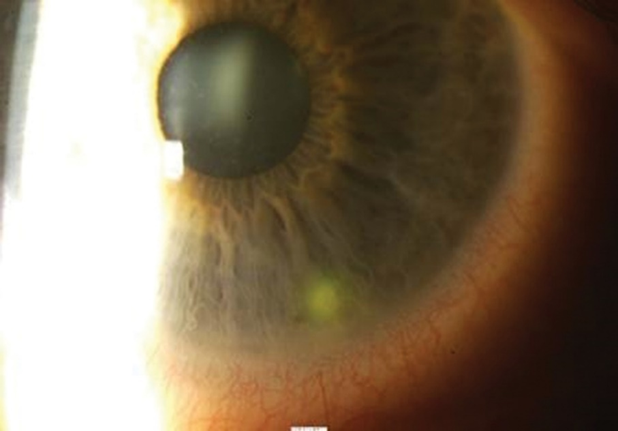

what are the signs of ocular rosacea (4:4)

ā¢Hyperaemic thickened lids

ā¢Telangiectasia (small, dilated blood vessels that are visible) of lid margins

ā¢Chronic blepharitis (MGD)

ā¢Recurrent chalazion/hordeolum

ā¢Tear film instability

ā¢Cornea (up to 30% of rosacea pts)

ā¢Punctate corneal staining (lower 1/3rd)

ā¢Corneal ulcers & thinning (can perforate)

ā¢Ultimately peripheral neovascularisation and scarring